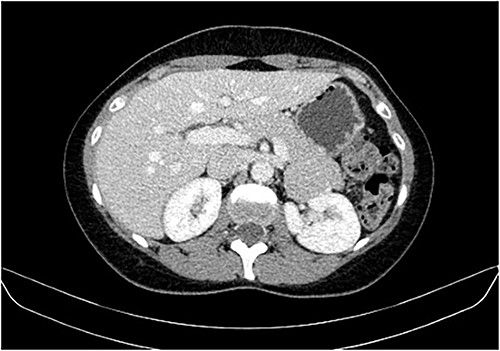

During a screening imaging examination of her liver disease, a lesion suspected of malignancy was detected. The ultrasound disclosed a hypoechoic nodule, vaguely heterogeneous, located in segment VII, subcapsular, and with ~22 mm in diameter (Fig. 1). Liver blood tests and serum alpha-fetoprotein level were normal. For better characterization, a CT scan was performed. The CT showed, in addition to signs of chronic liver disease, the presence of a solid subcapsular nodule of segment VII, measuring 23 mm, with hypervascular behavior in the arterial phase (Fig. 2) and washout in late venous phase (Fig. 3).

CT scan showing, in addition to signs of chronic liver disease, the presence of a solid subcapsular nodule of segment VII, measuring 23 mm, with hypervascular behavior in the arterial phase.

CT scan showing the same mass as shown in Fig. 2 but with washout in the portal venous phase.